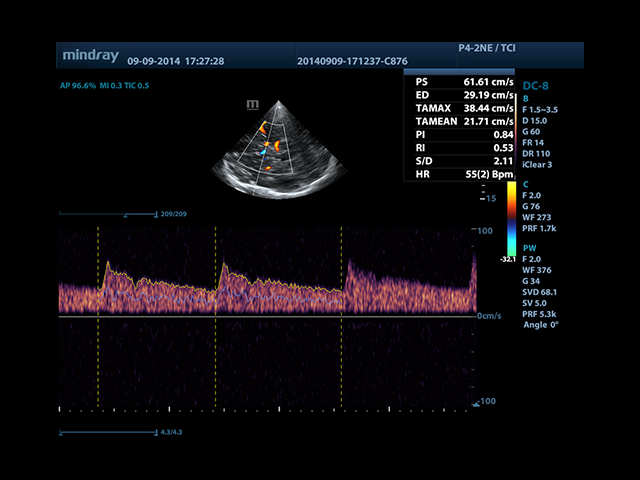

• Smart Doppler - автоматическая подстройка расположения рамки цветового доплера и контрольного объема импульсно-волнового доплера нажатием кнопки.

• Автоматическая трассировка допплеровского спектра с расчетом параметров и индексов

• Smart Doppler™ - автоматическая подстройка расположения рамки цветового допплера и контрольного объема импульсно-волнового допплера

• Секторный датчик Mindray P4-2E